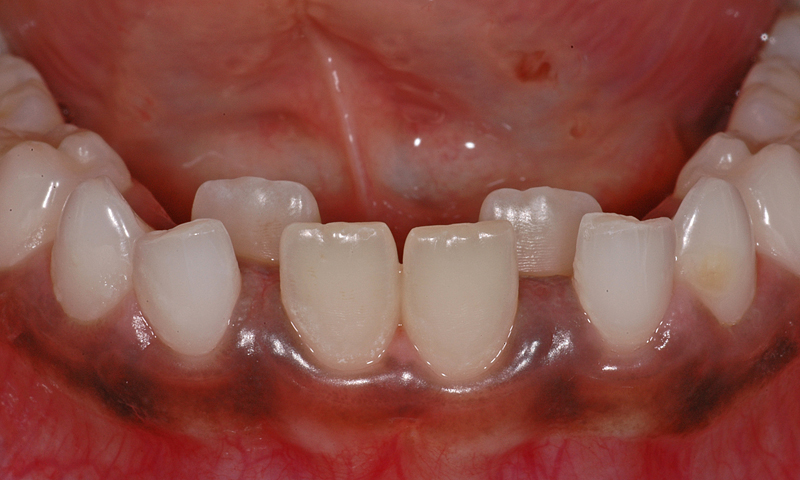

Durchbruch bleibender Zähne bei vorhandenen Milchzähnen

Anbei zeige ich einen ganz ähnlichen Fall, bei dem aber die seitlichen Schneidezähne im Unterkiefer betroffen sind.

Der Patient ist knapp 8½ Jahre alt, das Bild zeigt den Zustand, wie er sich bei der Erstkonsulation präsentierte. Die bleibenden Zähne sind schon sehr weit, fast ganz, durchgebrochen. Die Milchzähne sind noch komplett fest. Daher haben wir uns entschieden, die Milchzähne demnächst zu entfernen, damit die bleibenden so gut als möglich an die «richtige» Stelle kommen können.

Oft genügt der Zungendruck allein, damit sich die bleibenden Zähne im Laufe der Zeit in die Zahnreihe stellen. Wenn die bleibenden Zähne noch früher im Durchbruch sind, ist es in der Regel eher so, dass sie an die richtige Position kommen. Im vorliegenden Fall wird sich zeigen müssen, ob die Natur diese «Fehlstellung» von selbst komplett zu korrigieren vermag; immerhin ist genügend Platz vorhanden. Die Entfernung zu einem schon etwas früheren Termin wäre hier sicher hilfreich gewesen.